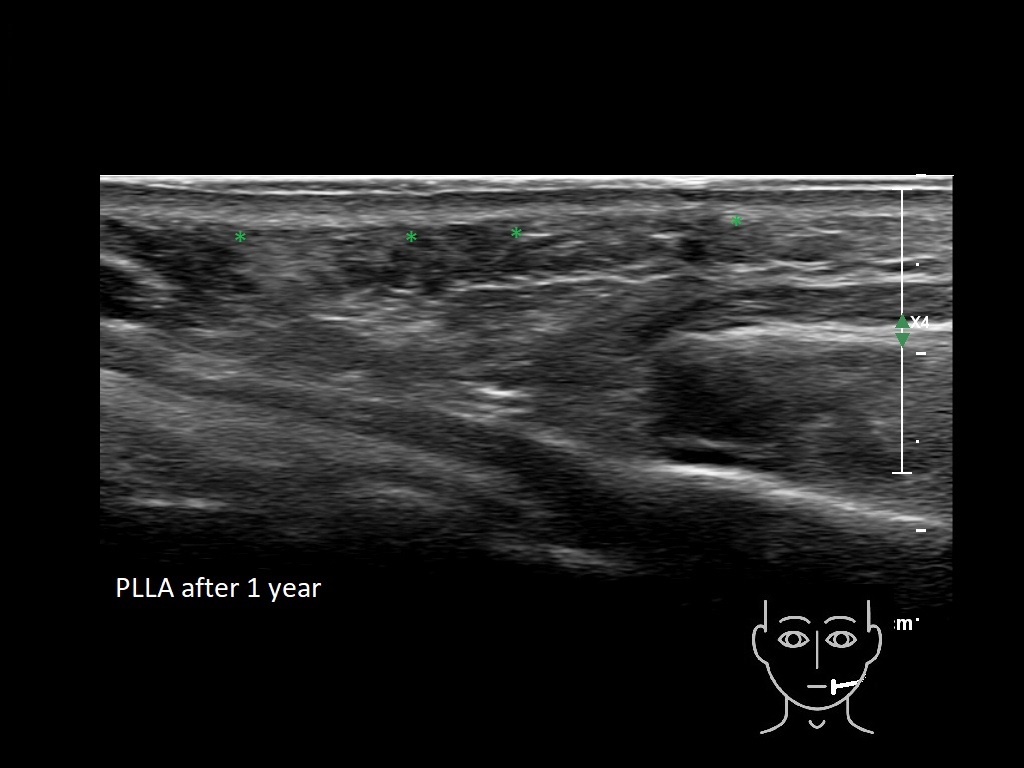

Draw in the second image below where the fillers are located. To check if your answer is correct, swipe the first image to the right.